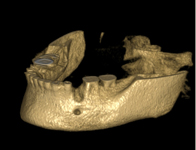

SonicWeld Rx

Novinkou v augmentačních metodách, kterou jako první v České republice používáme v našem zařízení je ultrazvuková metoda pomocí polylaktidové membrány - SonicWeld Rx®, kterou zavedl do implantologie v roce 2009 Dr. Dr. G.Iglhaut (Memmingen, Německo).

Jedná se o augmentační metodu při dostavbách kosti a defektech kosti horní a dolní čelisti.